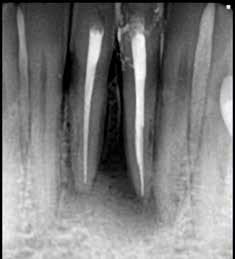

Krell és Caplan kutatásában 2086 repedt fogat vizsgáltak meg. A vizsgált fogak között leggyakrabban a második alsó nagyőrlőfogak (36%), majd ezt követően az első alsó nagyőrlők (27%), és végül az első felső nagyőrlők (18%) fordultak elő. A kutatási eredményeik szerint a fogbél állapota nem befolyásolta jelentős mértékben a kezelés várható kimenetelét. (Irreverzibilis pulpitis 85%; necrosis 80%; korábban gyökérkezelt 74%). A kimenetel szempontjából ugyanígy indifferens volt a páciensek neme, életkora, a kezelés időpontja, a fog pozíciója, a fog helyreállítása során használt anyag típusa, valamint az érintett fogfelszínek száma. 2014 júliusában egy 45 éves hölgy páciens azzal a panasszal kereste fel a rendelőnket, hogy nagyjából 10 napja egy fájdalmas duzzanat alakult ki a jobb felső első kisőrlője koronája mellett (14). A klinikai vizsgálat során egy amalgámtömést találtunk a panaszos fogban. A tömés széli zárása nem volt megfelelő, a disztális záróléc és a tömés között rést tapasztaltunk. A fog disztobukkális és linguális felszíne mellett 8 mm-es csontos tasakokat mértünk. A periapikális felvételen az 14-es foggyökér disztális felszínének megfelelően vertikális irányú radiolucens felritkulást észleltünk. A klinikai vizsgálat során a mesiális zárólécet kettéválasztó törésvonalat detektáltunk (17–18. ábra). A fogszenzibilitás vizsgálata során negatív eredményt kaptunk. A páciensnek ismertettük az elérhető terápiás lehetőségeket: 1, a 14-es fog eltávolítása, majd a foghiány 3 tagú cementezett híddal történő pótlása; 2, a 14-es fog eltávolítása, kemény- és lágyszöveti augmentáció, majd implantátum behelyezése; 3, a 14-es fog gyökérkezelése, gyökértömése és ezt követően a csücsökborítást biztosító restaurátum készítése. Arra is felhívtuk a páciens figyelmét, hogy a 3. terápiás lehetőség választása esetén nem tudjuk a fogmegtartás sikerességét garantálni, de végül – főként anyagi okok miatt – mégis ezt a terápiás opciót választotta. Fontos megjegyezni, hogy a repedt fogak ellátási lehetőségeit a törésvonal mélysége, elhelyezkedése, lefutása nagyban befolyásolja. A kezelés megtervezése során a fog és a fogat körülvevő szövetek állapotával kapcsolatos számtalan különböző faktort kell egyidejűleg figyelembe vennünk. A gyökérkezelést követően a gyökértömést meleg vertikális kondenzációs technikai alkalmazásával készítettük el (19. ábra). A hozzáférési nyílást folyékony és hibrid kompozit tömőanyag segítségével zártuk. A zárás elkészítése során a dr. David Clark által kifejlesztett Bioclear matricarendszert alkalmaztuk. A 6 éves kontroll során készített (2020) röntgenfelvételen a csontos defektus telődése volt megfigyelhető. Ez is a parodontális defektus gyógyulását igazolta (20–21. ábra).

17. ábra: A 14-es fog gyökerének disztális felszíne mellett vertikális csontpusztulásra utaló jelek észlelhetőek. Klinikailag ezen a területen 8 mm mélységű tasakmélységet mértünk. – 18. ábra: A 14-es fog disztális zárólécének megfelelően törésvonal észlelhető, ugyanakkor a csücskök teljes szeparálódására utaló jelek nem láthatóak. Az amalgámtömés eltávolítását követően jól megfigyelhető volt a törésvonal teljes lefutása. – 19. ábra: A gyökértömés elkészítése során meleg vertikális kondenzációs technikát alkalmaztunk. A felvételeken oldalcsatornák jelenlétére utaló jelek is észlelhetőek. – 20–21. ábra: A 2020-ban készült kontrollfelvételeken jól látható a csontos defektus telődése. A radiológiai jelek alapján (jól lekövethető gyökérhártyarés) a parodontális ligamentumok regenerációját is vélelmezzük.